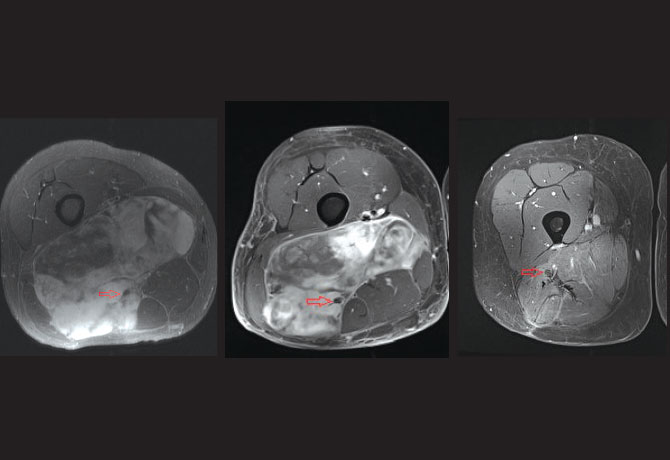

The patient, a 31-year-old father of two young children, had been living with a mass in his right thigh for more than two years. He initially thought it was a growing muscle, but when the mass started to grow quickly and cause shooting pains into the foot, he suspected that something was wrong. An MRI was obtained showing a very large mass in the thigh that was suspicious for a cancer. The tumor was encasing the sciatic nerve and abutting the popliteal vessels (Figure 1).

Dr. Iofin discussed with the patient the possibility of having to remove the nerve with the tumor to rid the patient of his cancer, which would lead to numbness in the foot and the need to wear a brace. However, because myxoid liposarcoma is very sensitive to radiation, the patient was referred for radiation prior to surgery in an attempt to shrink the cancer and free up the sciatic nerve. After five weeks of radiation, the tumor got smaller, and an MRI showed that the sciatic nerve was at the edge of the tumor rather than running through it (Figure 2).

The decision about whether to save or remove the sciatic nerve would be made during surgery. At the time of surgery, Dr. Iofin carefully explored the sciatic nerve and its branches and found that the radiation had shrunk the tumor sufficiently and the nerve was free of cancer. The tumor was removed in its entirety.

The patient recovered well after the surgery. His sciatic nerve functions without a problem, he has returned to his job and family life with his wife and children, and he follows up regularly with Dr. Iofin. As seen on the most recent MRI (Figure 3), the patient has been cancer-free for more than a year.